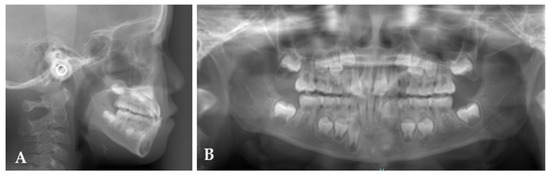

2. Case Report